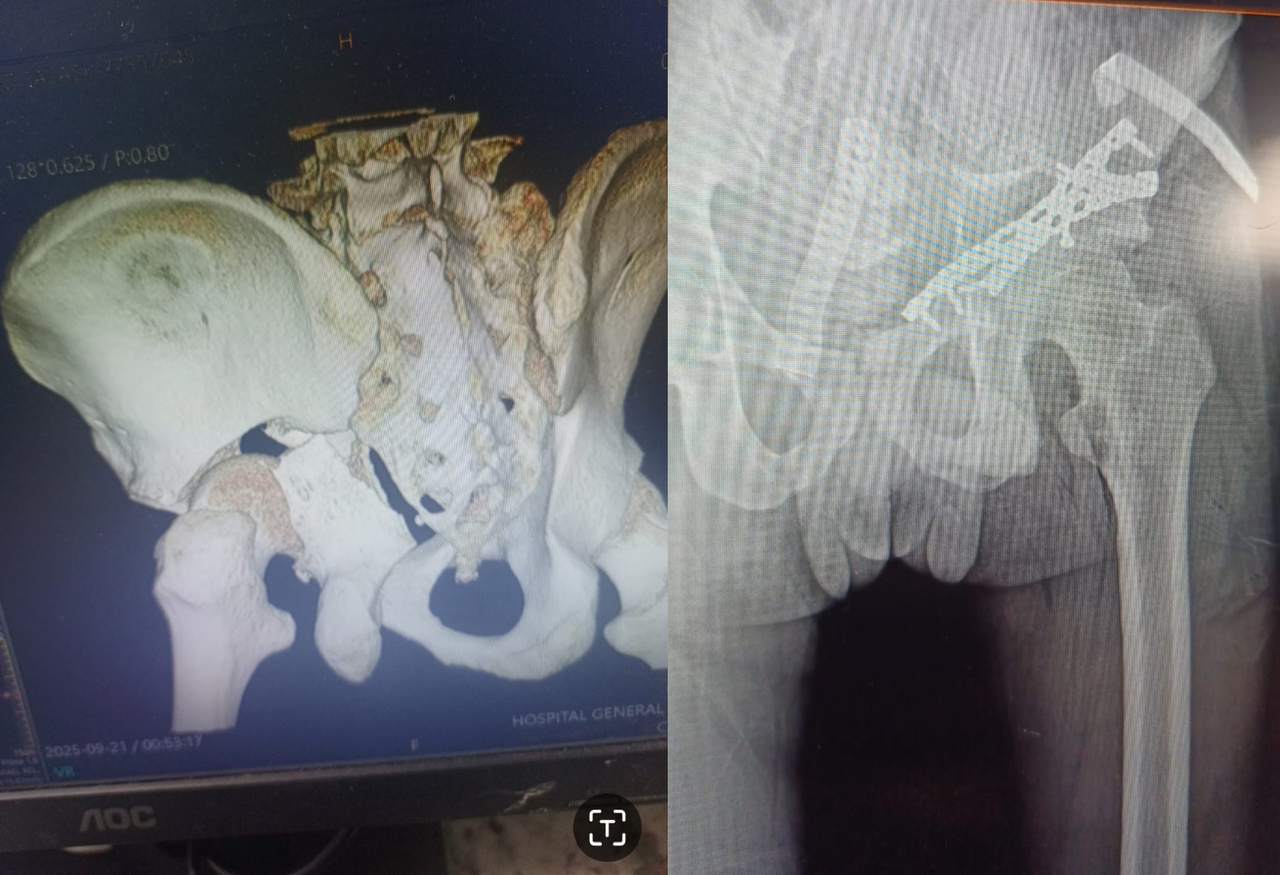

Fractura lateral de cadera izquierda

Ruptura del hueso en la parte externa de la cadera izquierda, generalmente causada por caídas o traumatismos, que provoca dolor y dificultad para caminar.

2

Cirugía exitosa

Se realiza reducción y aplicación de un DHS para estabilizar la fractura